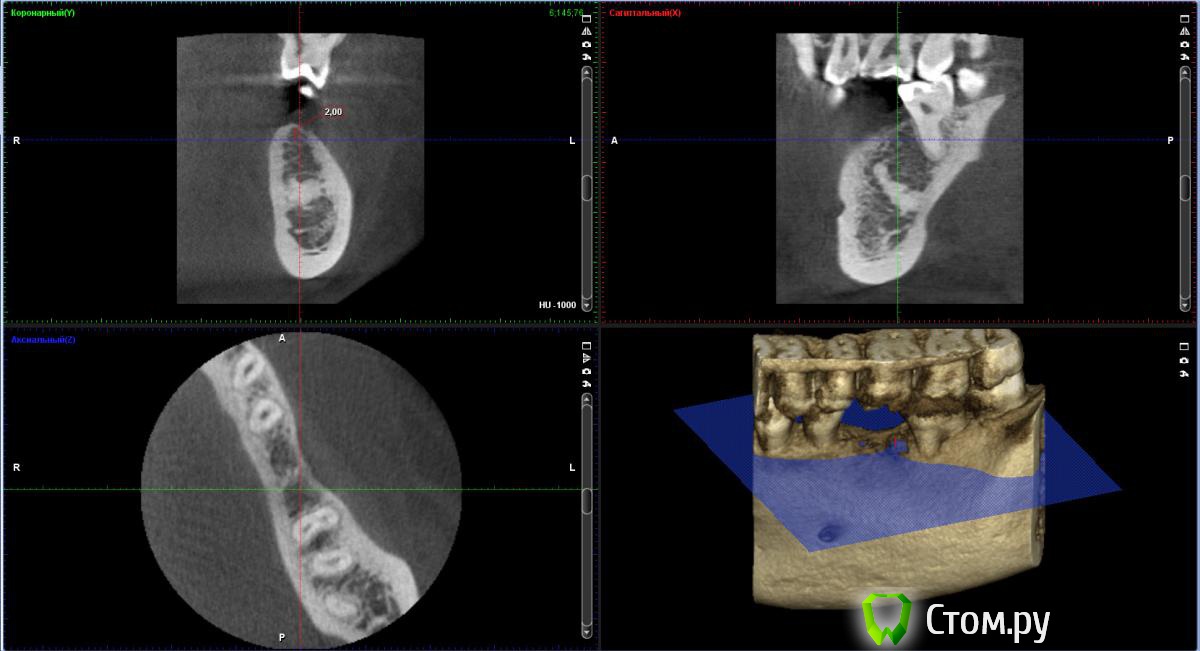

bobrdobr Опубликовано 17 февраля, 2014 Автор Поделиться Опубликовано 17 февраля, 2014 Добрый всем день. Сделал КТ. Снимок выложил на Яндекс.Дискhttp://yadi.sk/d/-CHDNu-nJ45Wy Посмотрите пожалуйста. Вопрос прежний: нужна ли костная пластика в каком-то виде перед установкой винтового импланта? Ссылка на комментарий

Bier Опубликовано 17 февраля, 2014 Поделиться Опубликовано 17 февраля, 2014 судя по фото, скорее всего нужна. От КТ нужен срез горизонтальной плоскости - вид сверху на костный гребень, на 1 мм ниже его вершины. Ссылка на комментарий

bobrdobr Опубликовано 18 февраля, 2014 Автор Поделиться Опубликовано 18 февраля, 2014 (изменено) Имплант был предложен Semados 4,1*11,5 без костной пластики. судя по фото, скорее всего нужна. От КТ нужен срез горизонтальной плоскости - вид сверху на костный гребень, на 1 мм ниже его вершины. Сейчас попробую. Прикладываю 4 снимка: на уровне гребня (как мне кажется) и на 1,2,3 и мм. ниже. Изменено 18 февраля, 2014 пользователем bobrdobr Ссылка на комментарий

Bier Опубликовано 18 февраля, 2014 Поделиться Опубликовано 18 февраля, 2014 Можно поставить, одновременно добавив немного кости и закрыть мембраной. Кость можно даже взять прямо из того места, куда будет ставиться имплантат, т.е. доп травмы не будет Ссылка на комментарий

bobrdobr Опубликовано 18 февраля, 2014 Автор Поделиться Опубликовано 18 февраля, 2014 Можно поставить, одновременно добавив немного кости и закрыть мембраной. Кость можно даже взять прямо из того места, куда будет ставиться имплантат, т.е. доп травмы не будетБольшое спасибо за мнение! Ровно такой вариант предлагал хирург 3 под винтовой имплант. Правда, он же предложил байкон Что будет, если кость не подсыпать и мембрану не ставить? Ссылка на комментарий

Bier Опубликовано 18 февраля, 2014 Поделиться Опубликовано 18 февраля, 2014 Может и ничего не будет, если широкий диаметр не выбирать и десну подсадить, а может десна немного отойдет вниз через годик-другой. Ссылка на комментарий

bobrdobr Опубликовано 18 февраля, 2014 Автор Поделиться Опубликовано 18 февраля, 2014 Все ясно, благодарю. Диаметр 4,1 мм предлагают (Semados). Нормально для жевательного зуба? Ссылка на комментарий

Bier Опубликовано 18 февраля, 2014 Поделиться Опубликовано 18 февраля, 2014 Тогда подсыпать однозначно нужно, 4,1- стандартная платформа. Лучше сюда ставить тонкую платформу. Неважно какой зуб, они держат нагрузку. Главное чтобы кость была вокруг имплантата. Ссылка на комментарий